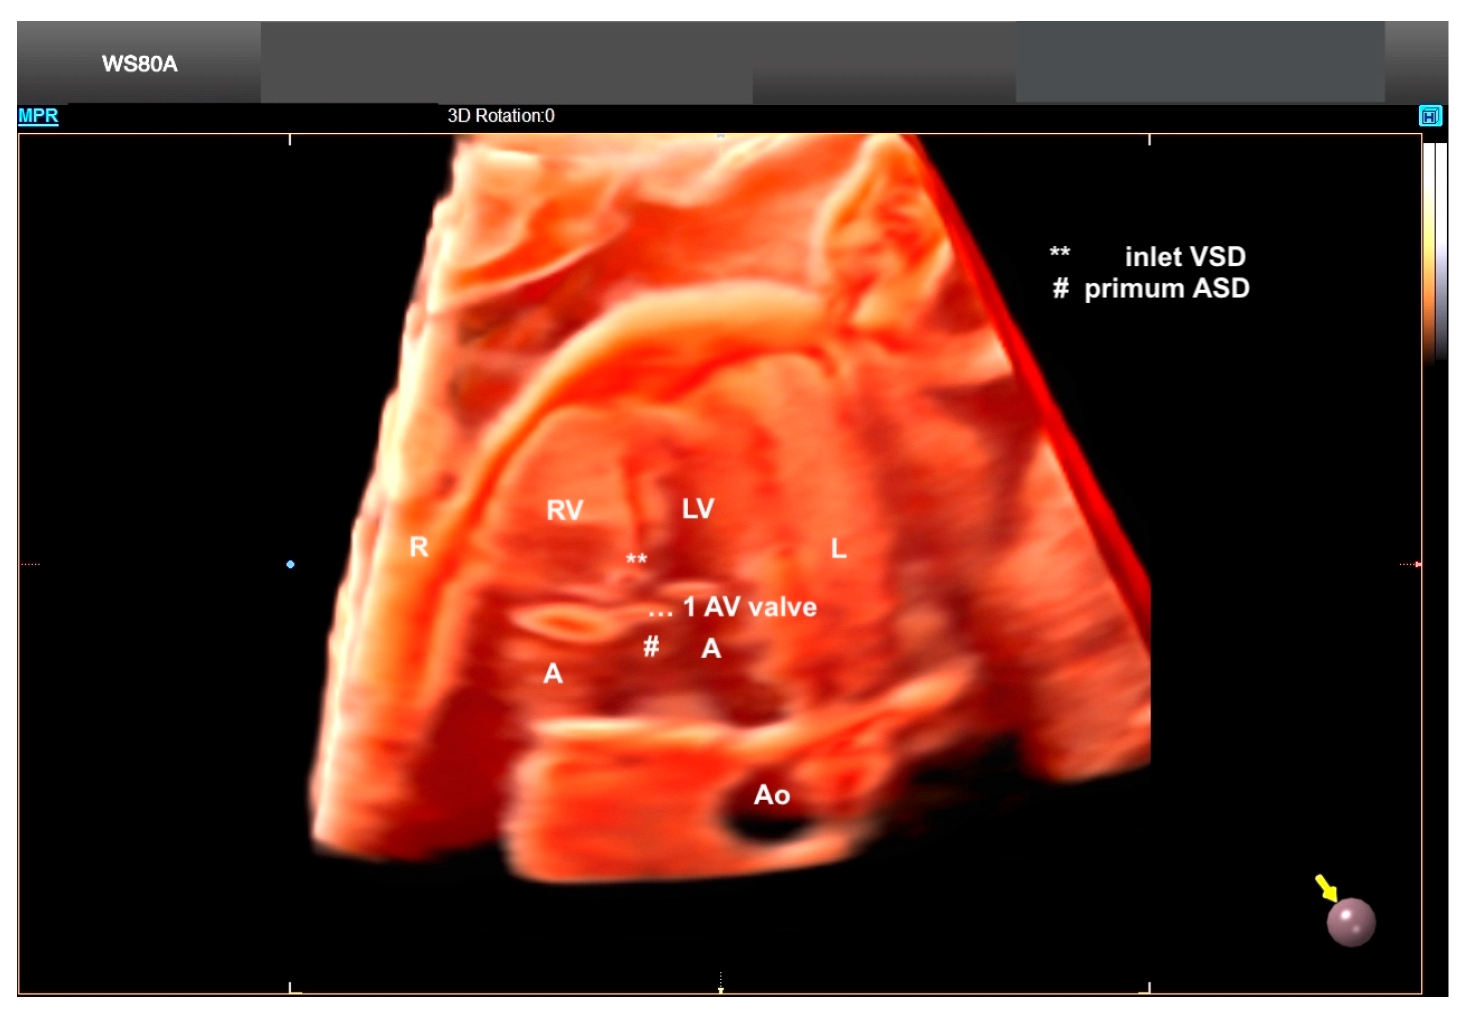

7. Isomerism

8. Atrioventricular Septal Defect

9. Tetralogy of Fallot